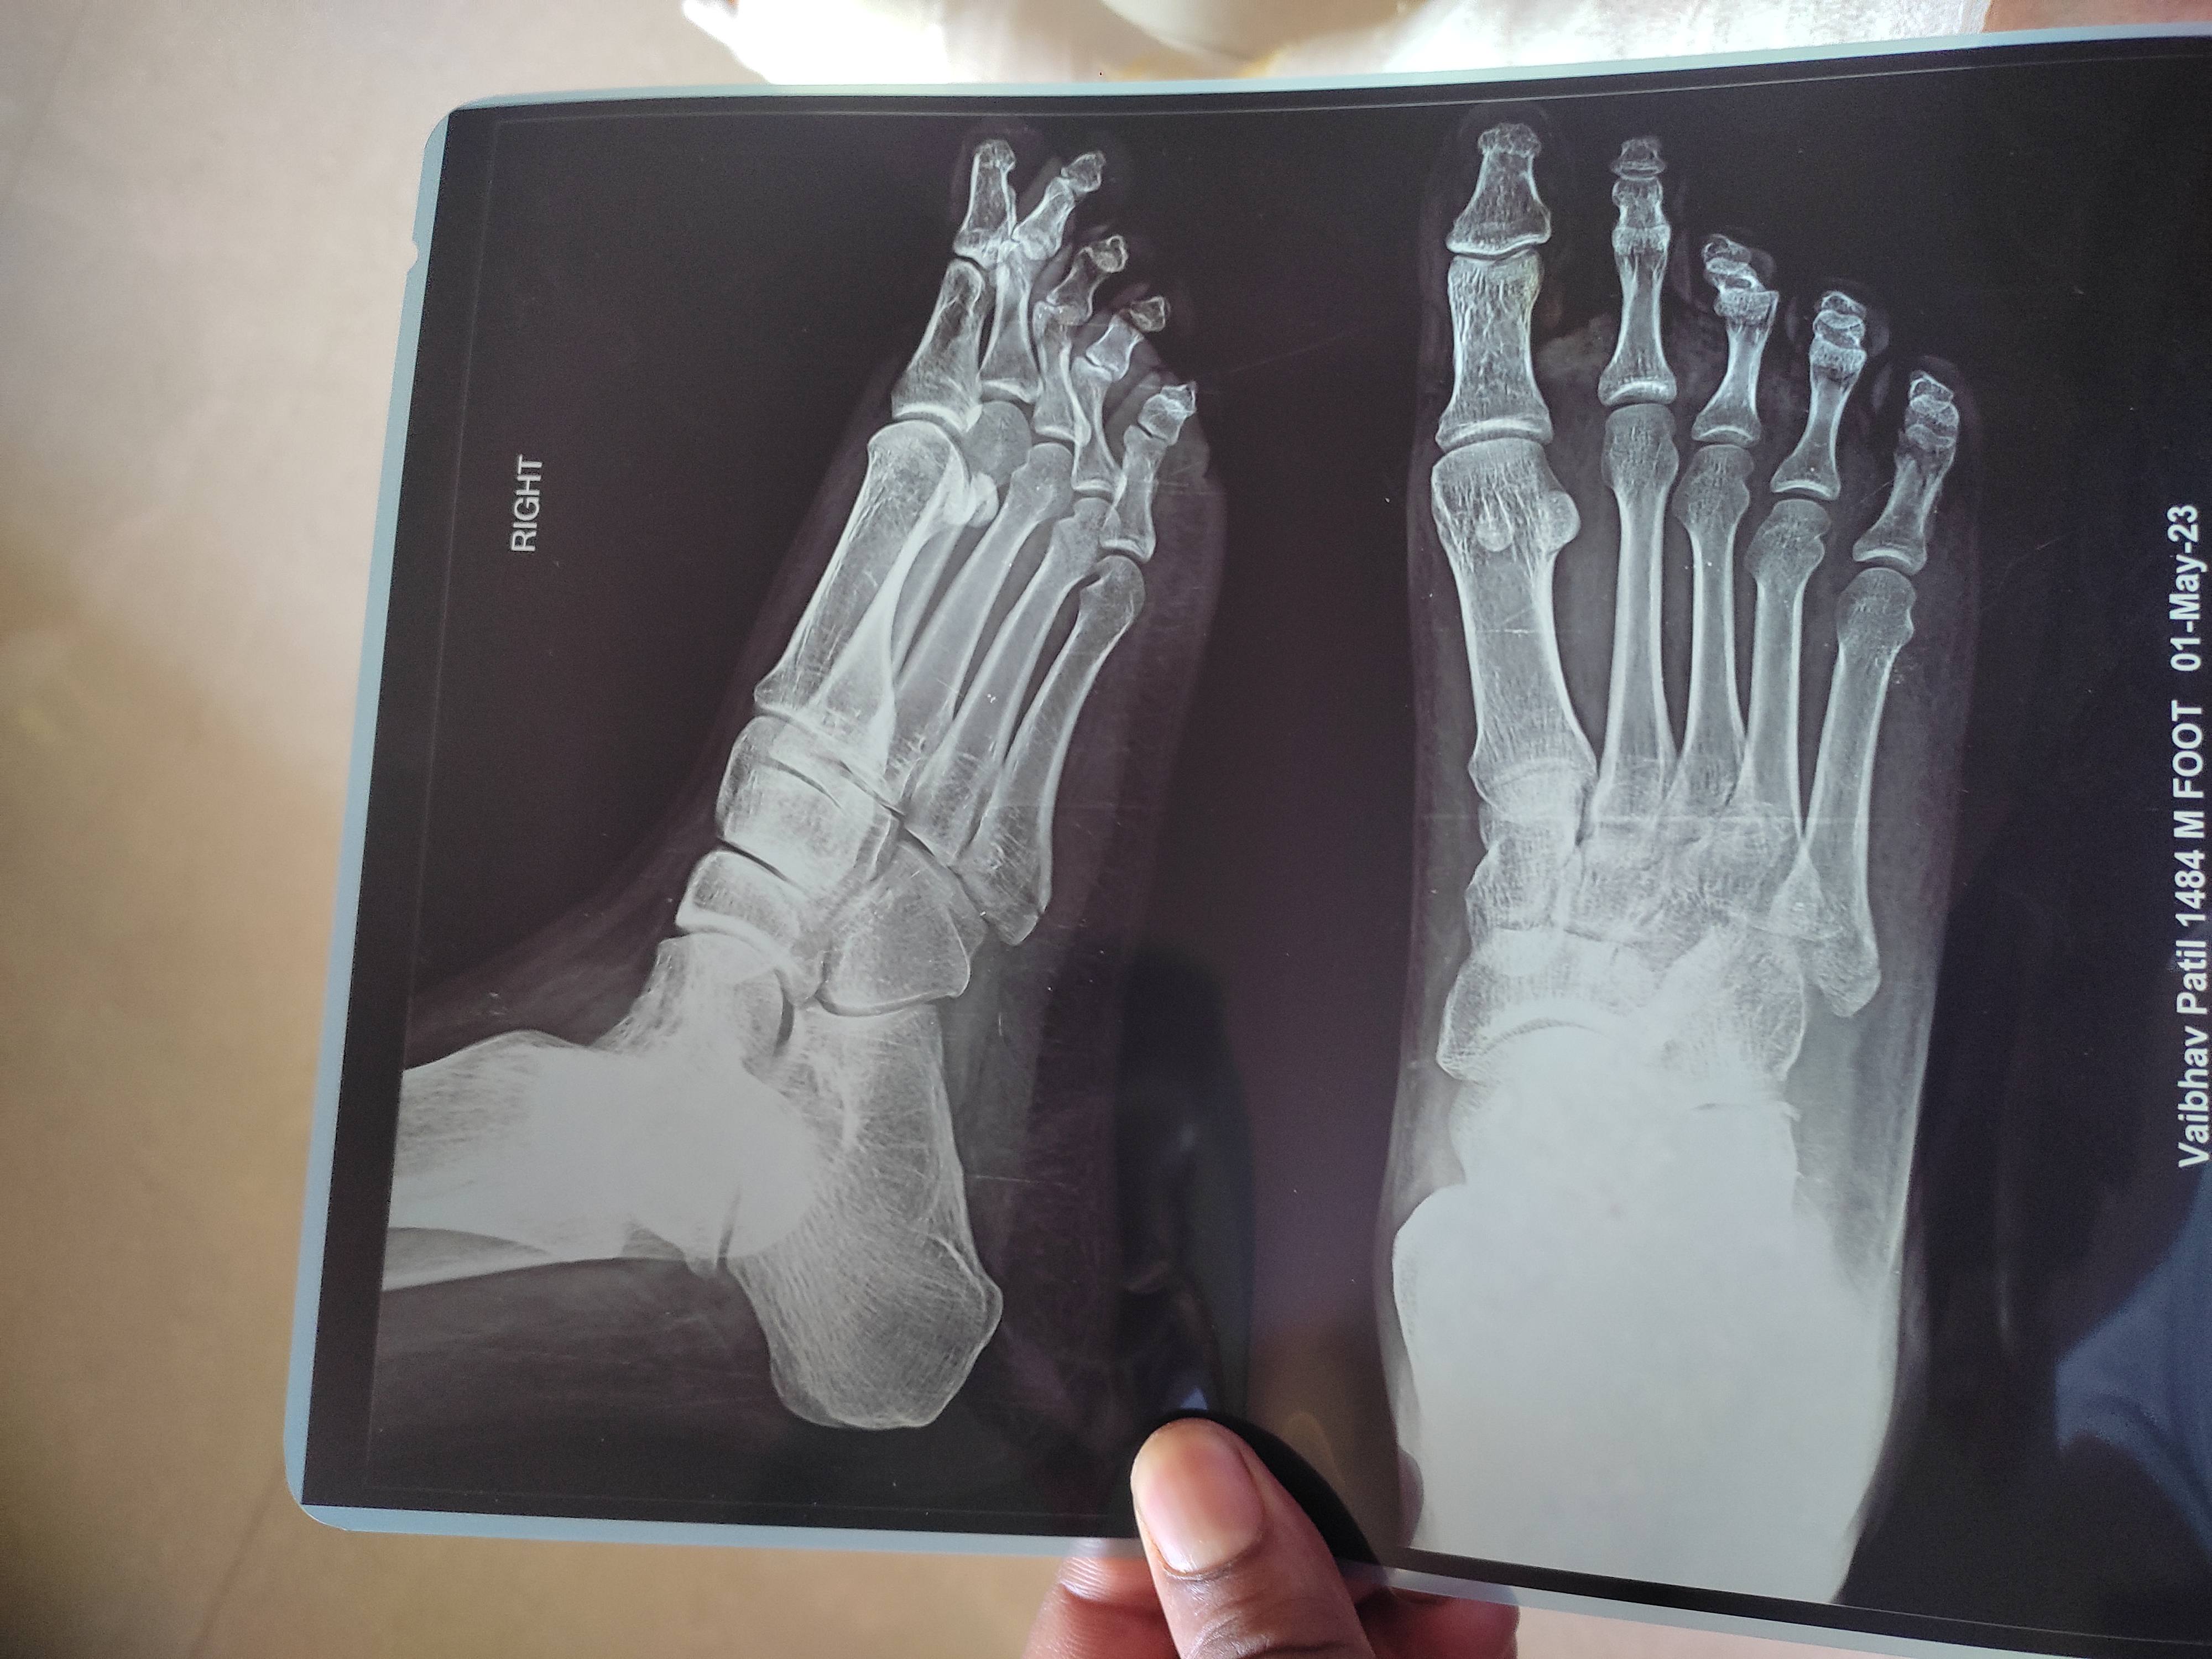

Sprain issue please advice...

Vaibhav patil